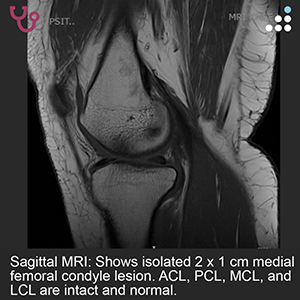

ISOLATED MEDIAL FEMORAL CONDYLE LESION IN 38F

HPI: The patient is a 38-year-old female office worker who presents with medial knee pain and moderate swelling following an acute sports-related injury sustained while playing Cabbageball. She is now 3 to 4 months out from the initial injury with persistent symptoms. She desires to return to her prior level of full sports activity.

PE: On physical exam, the patient has 3-4 degrees valgus bilaterally. There is a mild effusion about the left knee. ROM of the left knee is 0-130 degrees. There is a normal drawer, pivot shift, and Lachman’s test.